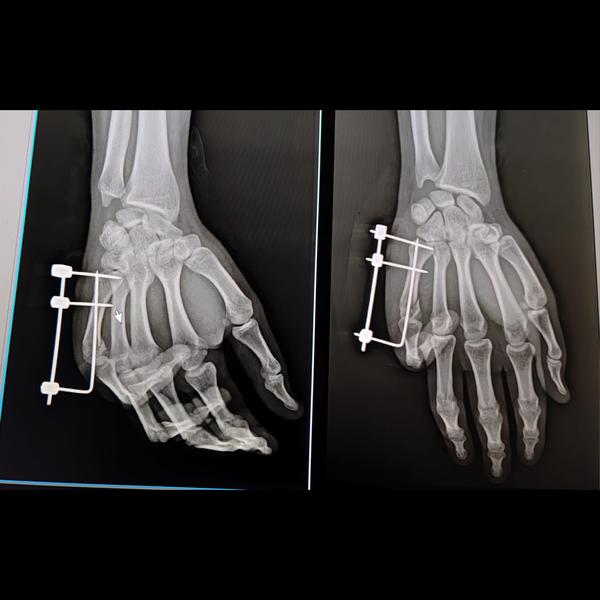

Fifth metacarpal fracture fixed with JESS fixator..No post operative finger stiffness,early recover...

View Details